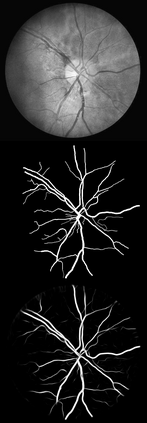

U-Net has been providing state-of-the-art performance in many medical image segmentation problems. Many modifications have been proposed for U-Net, such as attention U-Net, recurrent residual convolutional U-Net (R2-UNet), and U-Net with residual blocks or blocks with dense connections. However, all these modifications have an encoder-decoder structure with skip connections, and the number of paths for information flow is limited. We propose LadderNet in this paper, which can be viewed as a chain of multiple U-Nets. Instead of only one pair of encoder branch and decoder branch in U-Net, a LadderNet has multiple pairs of encoder-decoder branches, and has skip connections between every pair of adjacent decoder and decoder branches in each level. Inspired by the success of ResNet and R2-UNet, we use modified residual blocks where two convolutional layers in one block share the same weights. A LadderNet has more paths for information flow because of skip connections and residual blocks, and can be viewed as an ensemble of Fully Convolutional Networks (FCN). The equivalence to an ensemble of FCNs improves segmentation accuracy, while the shared weights within each residual block reduce parameter number. Semantic segmentation is essential for retinal disease detection. We tested LadderNet on two benchmark datasets for blood vessel segmentation in retinal images, and achieved superior performance over methods in the literature. The implementation is provided \url{https://github.com/juntang-zhuang/LadderNet}